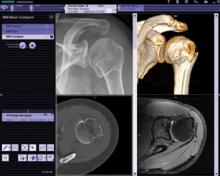

Once an emerging technology confined to early adopters, server-based advanced visualization has gradually become a more popular solution in the medical imaging informatics marketplace in the last few years. This has carried on to the point that it can today be deemed the de facto standard for advanced visualization in medical imaging enterprises.